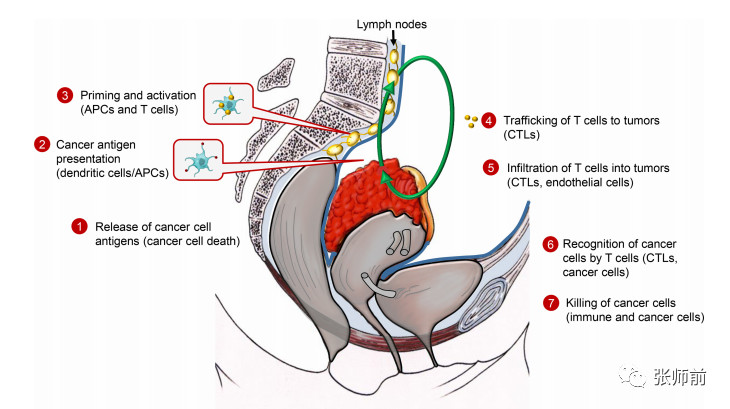

【摘要】肿瘤免疫疗法已经成为肿瘤学中最有希望的方法之一,肿瘤的免疫疗法包括激活免疫系统以诱导肿瘤免疫监视或逆转肿瘤免疫逃逸。近年来,卵巢癌的治疗策略发生了变化。早...